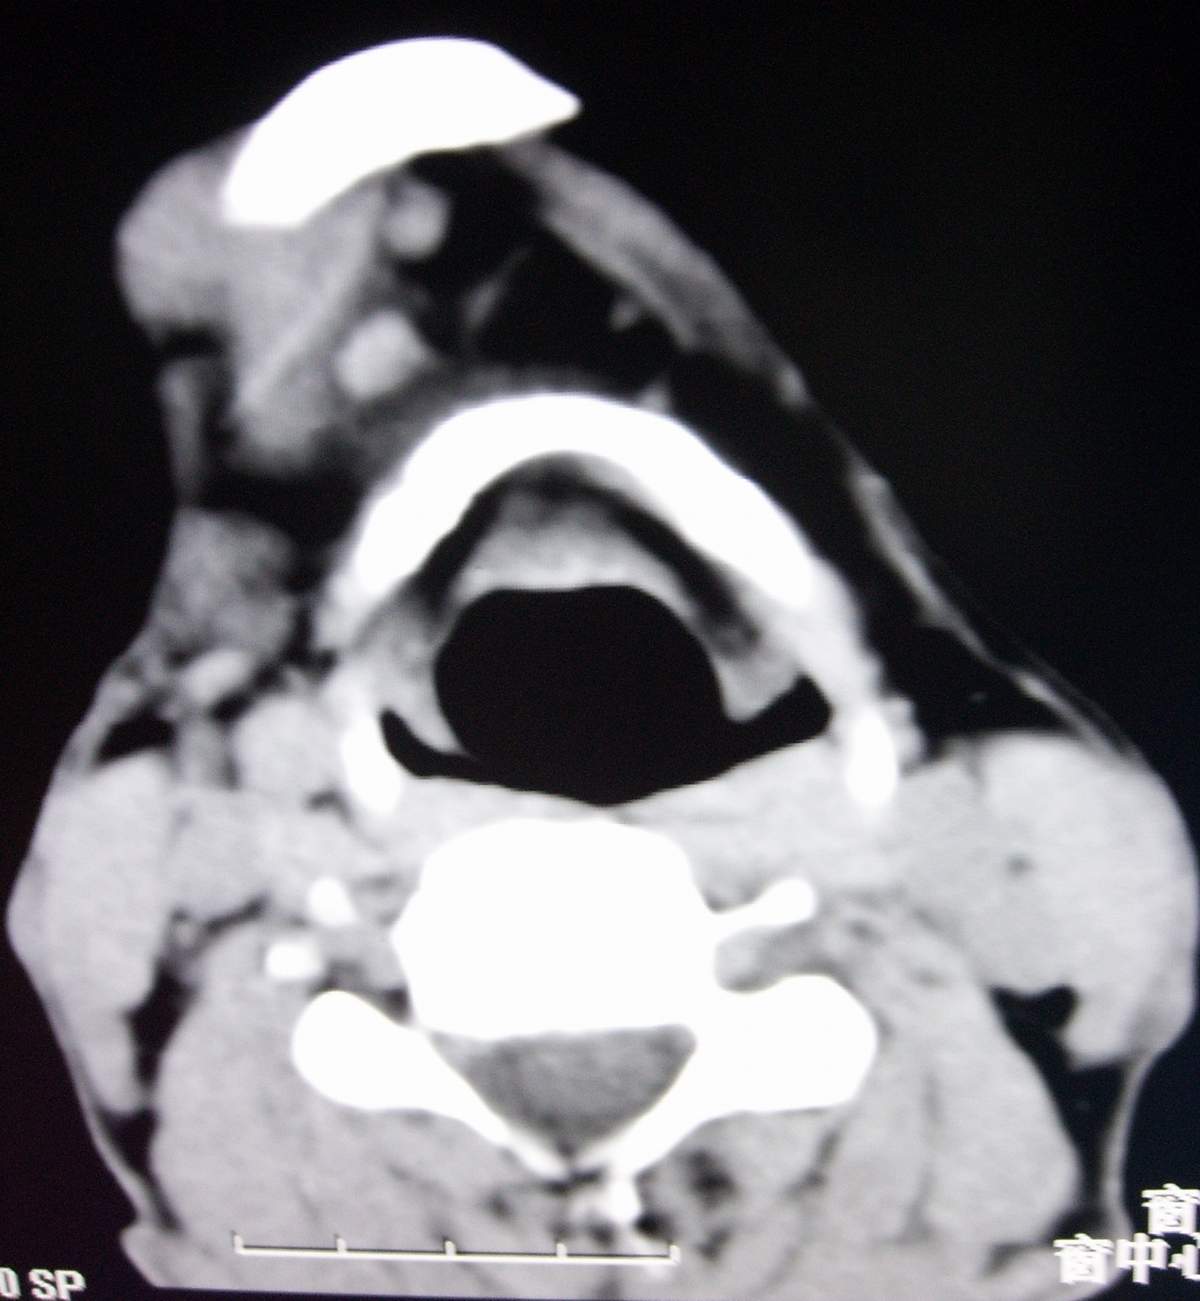

男,54岁,右下颌肿痛1月余。

右侧下颌骨水平部及升支呈溶骨性破坏,无明显膨胀,周围见软组织肿块。

考虑:右侧下颌骨恶性肿瘤或转移瘤。

右下颌骨溶骨性破坏,代之以团块状软组织影,内有斑片状瘤骨,边缘骨质有少量骨膜反应,考虑:右下颌骨骨肉瘤。期待病理。